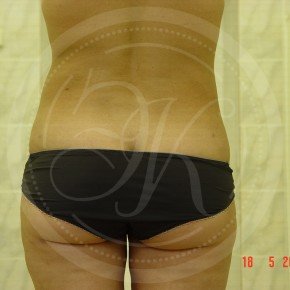

Фото до и после липосакции

В этой галерее мы публикуем снимки тех пациентов, которым была проведена липосакция. Фото до и после в полной мере позволяют оценить результат. Для каждого пациента мы подбираем тот вид вмешательства, который даст лучший результат при минимальном травматизме.